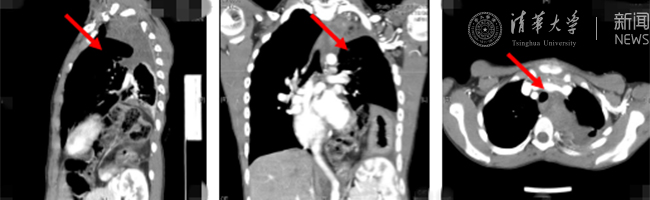

AG(中国)AG·官方网页版网8月30日电(通讯员 杨峰)如图中所示,本是正常人心脏、左肺的位置,被发于神经鞘的巨大肿瘤占据,导致一位刚满12岁的男孩胸痛、咳嗽、呼吸困难。近日,北京清华长庚医院神经外科与胸外科联手,由神经外科王贵怀主任主刀,成功为男孩切除胸腔巨大神经鞘肿瘤。

患者胸腔内巨大的肿瘤。

半年前,患者经常会出现胸痛、咳嗽和呼吸困难,在当地医院检查发现左侧胸腔巨大占位,左肺及心脏明显受压。王贵怀大夫接诊,仔细查体了解病情,并反复认真阅片后,认为左侧胸腔巨大肿瘤来自于胸椎椎管内,神经鞘瘤可能性大。该肿瘤体积巨大,占据绝大部分胸腔空间,压迫左肺、纵隔大血管及膈肌。